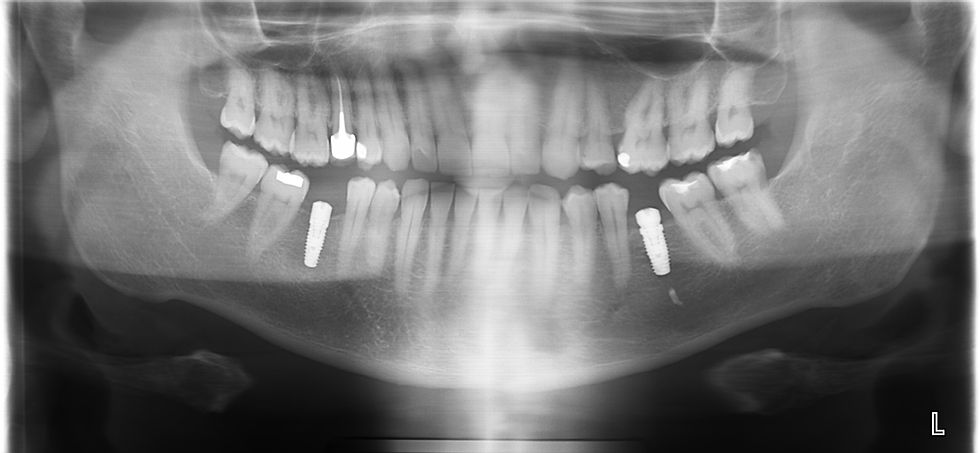

Cas clinique